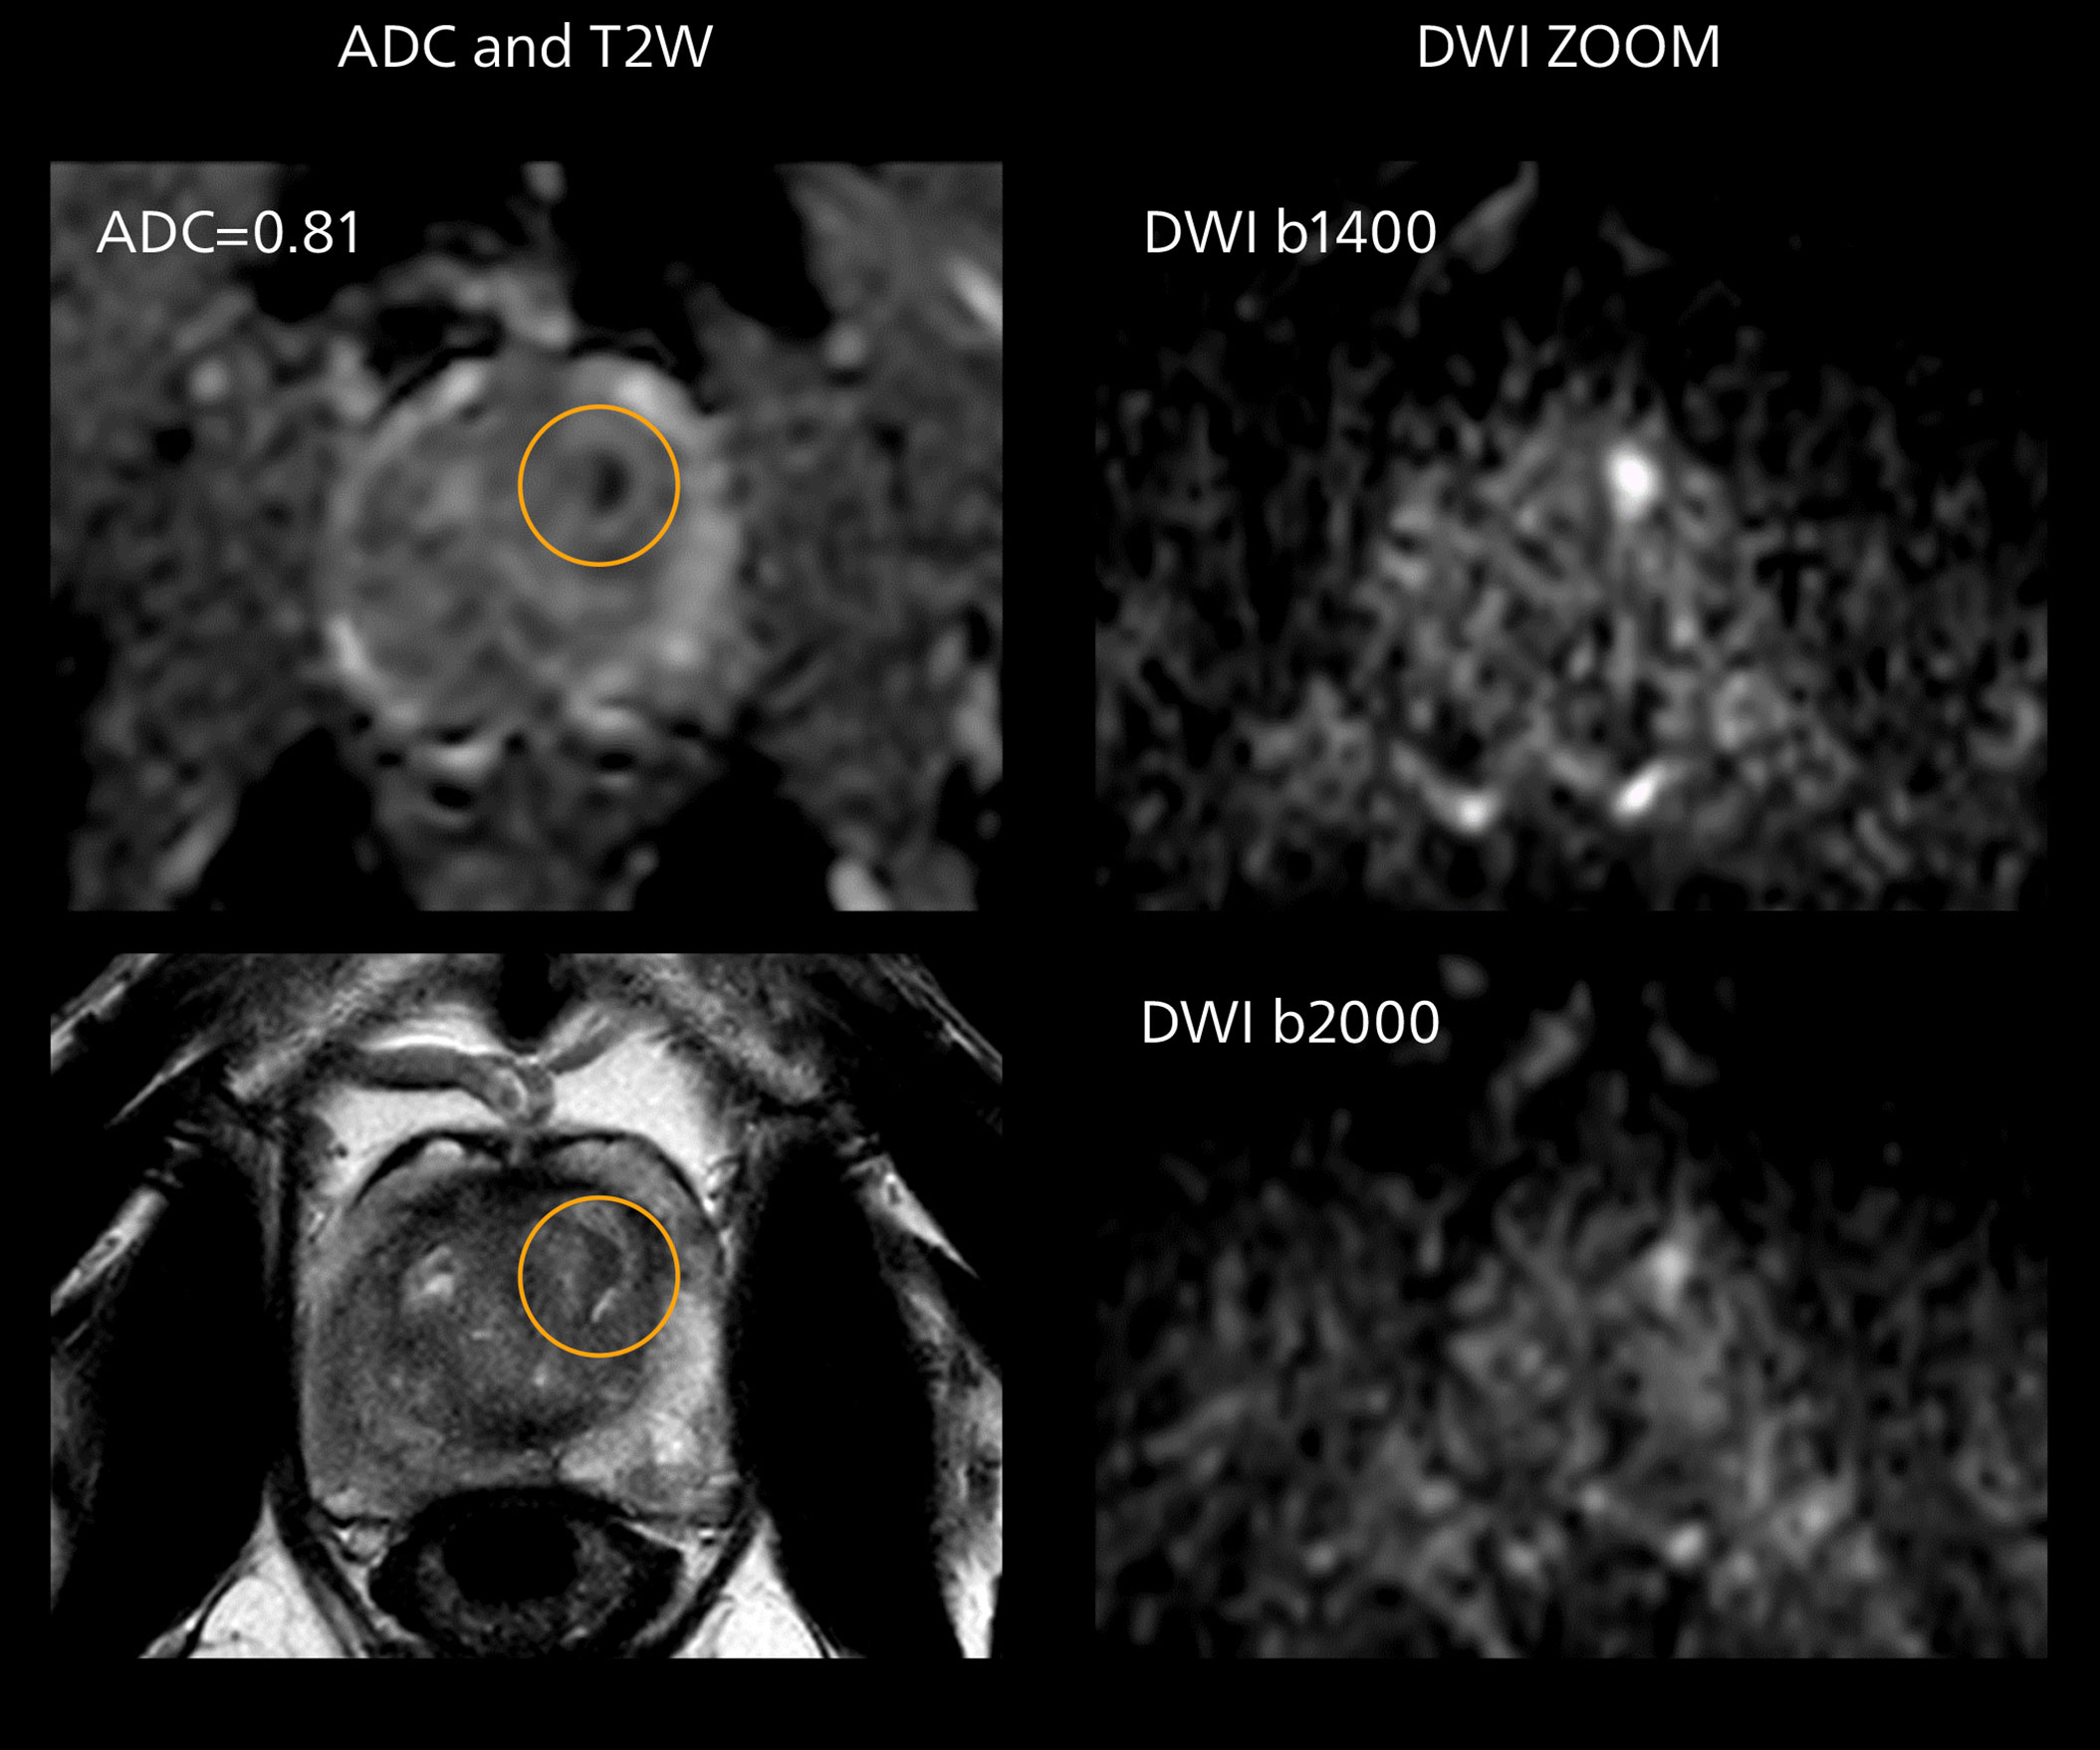

Diffusion weighted imaging of prostate

The examples on the left show the regular clinical diffusion protocol with four b-values up to b1000 s/mm². On the right, the T2W image shows a hypointense lesion that has low ADC and is clearly visible in b1400 and b2000 diffusion images, suggesting malignancy.

Diffusion weighted imaging of prostate

The examples on the left show the regular clinical diffusion protocol with four b-values up to b1000 s/mm². On the right, the T2W image shows a hypointense lesion that has low ADC and is clearly visible in b1400 and b2000 diffusion images, suggesting malignancy.